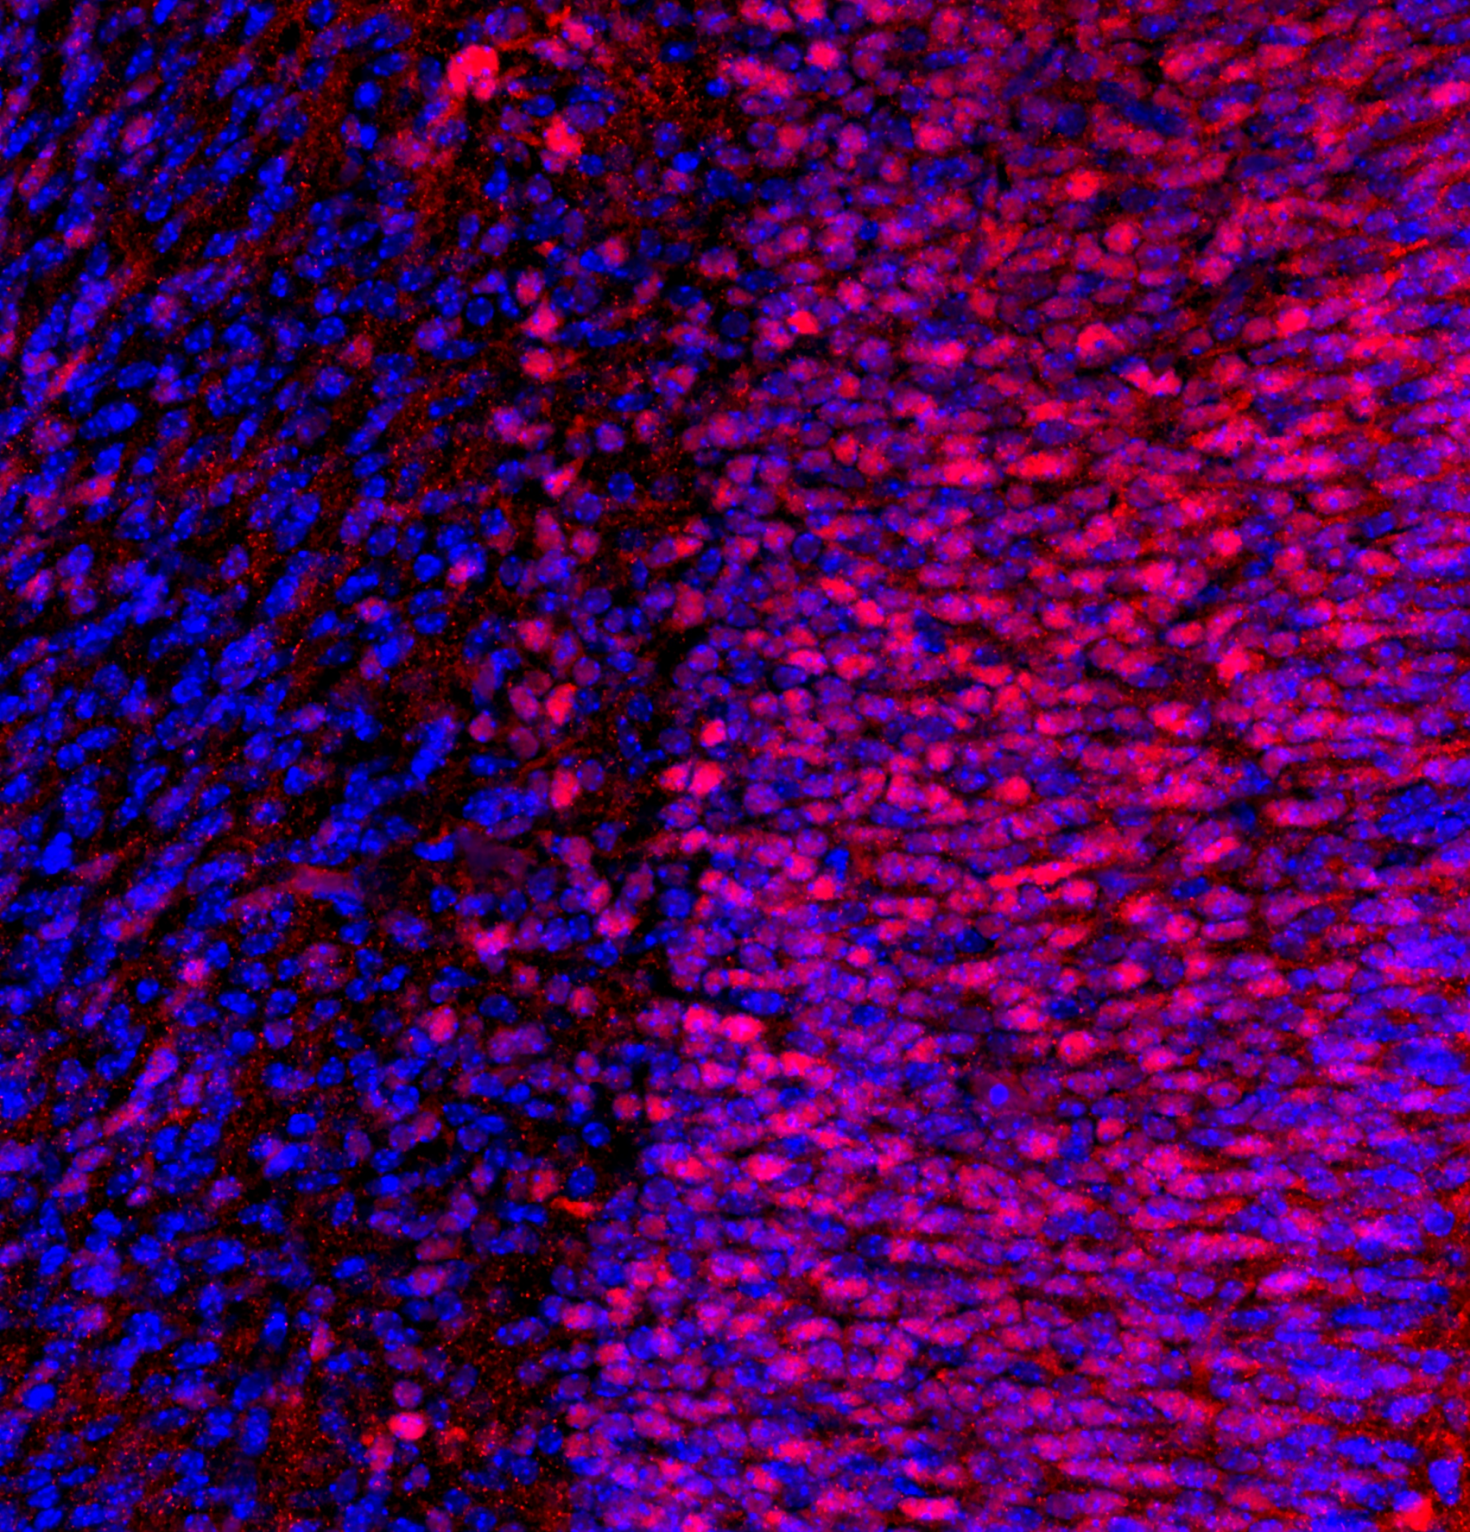

“The tissue is from a mouse uterus that was stained with a Ki-67 antibody. Ki-67 is a nuclear antigen that is expressed in cells that are in G1, S, G2, and mitosis, but not G0 marking the process of cell proliferation.”

Author: Adriana Andrus - Romana Nowak Lab